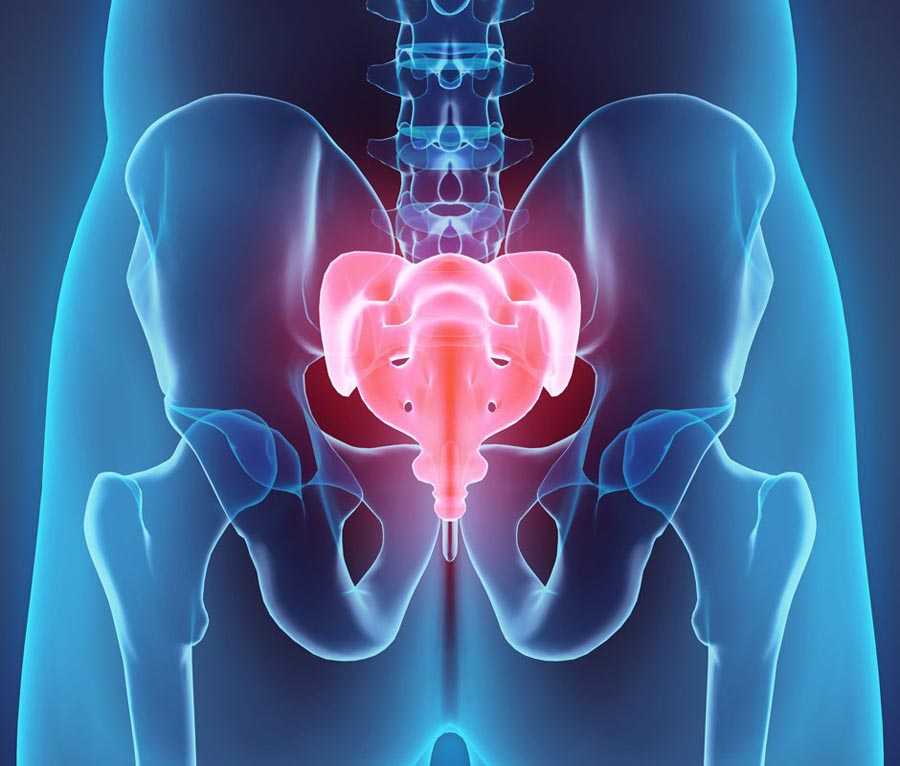

Рентгеновские снимки крестцово-копчикового отдела позвоночника